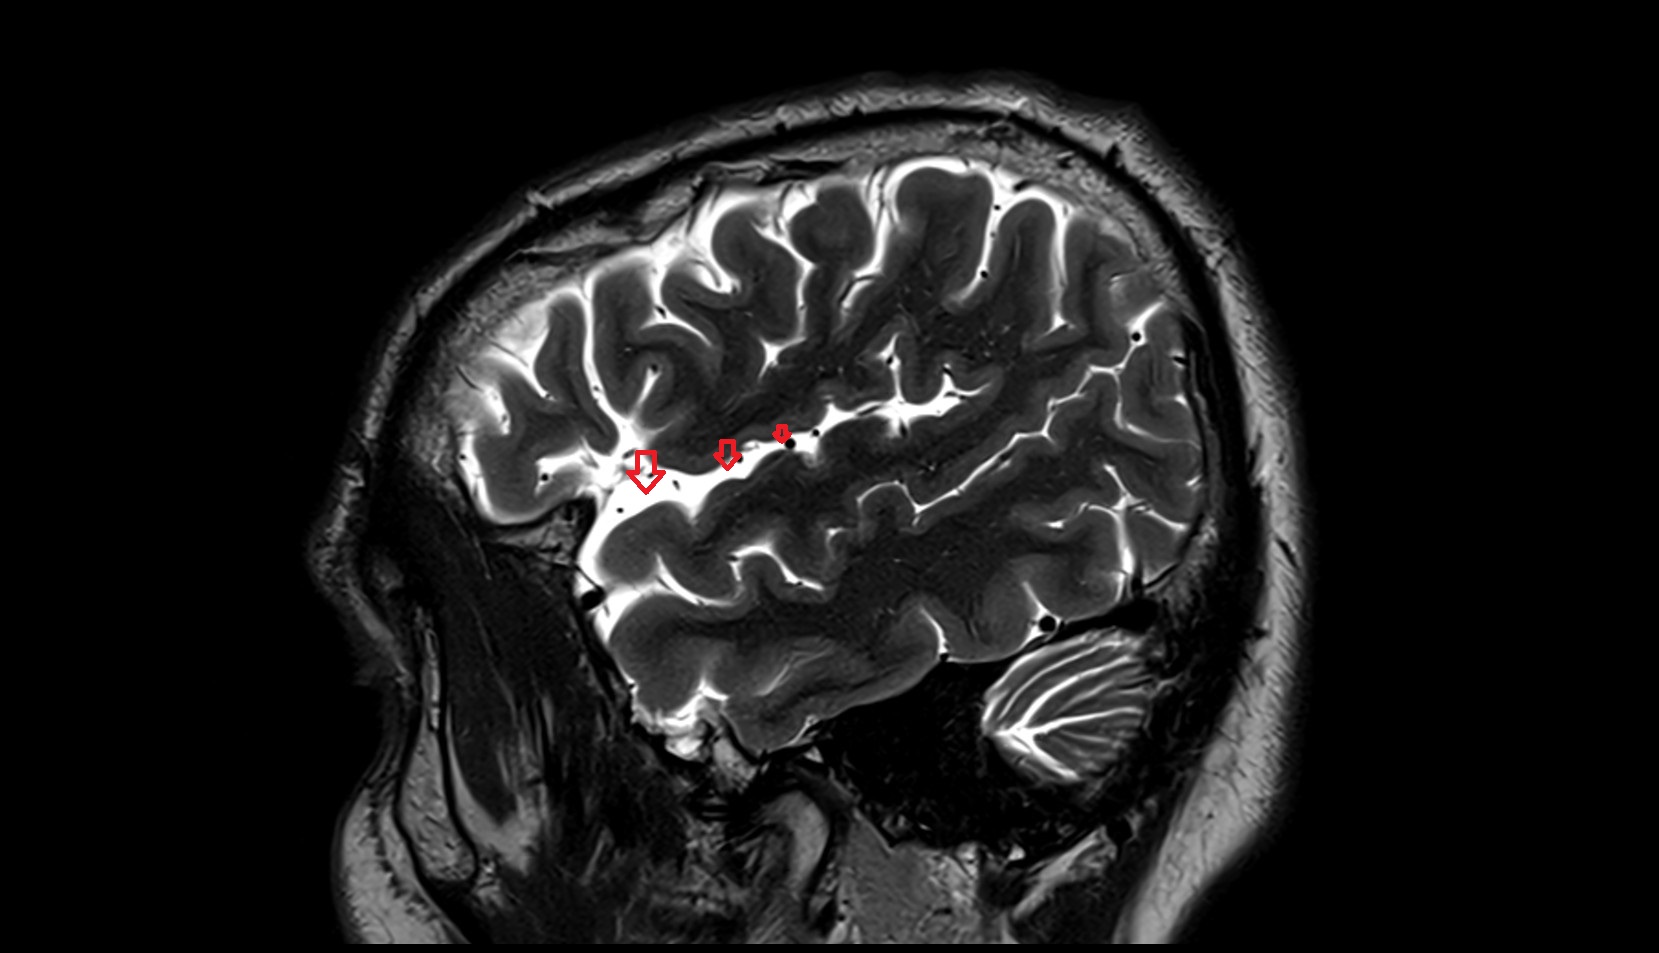

- Body of hippocampus

- Head of hippocampus

- Tail of hippocampus

- Hippocampus